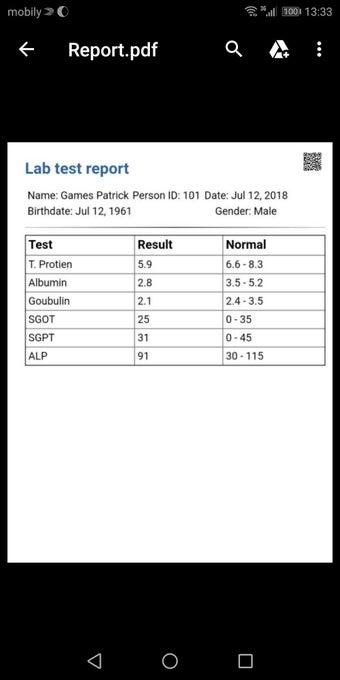

The Android Medical Records App by MedClin is a free medical records tracker app that allows users to store anamnesis, patient records, patient history, and health information. It is easy to use and provides numerous features such as username and password authentication, exporting medical data to Excel Sheet, and the ability to attach medical documents of any type. The app also has a smart search feature that allows users to search for patient information by name or ID, and even capture a photo for their profile.

In addition, the app has a blood pressure module that measures systolic, diastolic, and pulse, and allows users to export blood pressure reports to either PDF or graphs. The app also has a blood glucose (sugar) module that records blood sugar values and allows users to export blood glucose reports to either PDF or graphs. Users can also send blood pressure and blood sugar reports to their doctor. The app is compatible with multiple screens, including phones and tablets, and works on Chromebook systems. Overall, the Android Medical Records App is a great tool for patients and physicians alike for managing patient information and medical records.